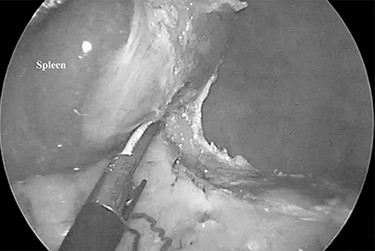

A 79-year-old female patient who had been diagnosed with chronic ITP in September 2014 presented at our hospital. She had received a combined therapy comprising prednisolone and thrombopoietin receptor agonist; however, her platelet count ranged from 0.5 to 59.9 × 104/ul and could not be controlled with oral therapy. Furthermore, she had comorbidities including hypertension, dyslipidemia and diabetes mellitus induced by pre-dnisolone, and a past history of cholecystectomy with an upper abdominal incision. She underwent NS in October 2015, and there were dense adhesions around the spleen supposing to the previous upper abdominal surgery (Fig. 1). The duration of surgery was 163 min and an intra-operative blood loss was 10 ml. Post-operative CT showed a low volume of ascites, which did not require further treatment. She was discharged on the post-operative day 9 with an extremely high her platelet count (135.2 × 104/ul). The weight of the resected specimen was 135 g. Her post-operative platelet count settled at around 45 × 104/ul during 54 months after surgery.

Dense adhesions around the spleen were divided under 3-mm needlescope.

Minimally invasive abdominal surgery performed with needlescopic instruments leads to minimal surgical trauma to the abdominal wall, improved cosmetic result, reduced postoperative pain, lower incidence of wound complication, no risk of port site hernia and earlier recovery. Initially, we used of 2-mm needlescopic instruments for laparoscopic splenectomy (LS); however, the shaft easily bent when manipulating the organs, and there is a high frequency of a butting between the 2-mm needlescope and another forceps due to close proximity to the organs, with a narrow angle of surgical view [2]. Therefore, we utilized 3-mm instruments to overcome the restriction of surgical optics and maneuverability and provide better convenience for the surgeons. However, the risk of tissue damage by the pointed ends of fine graspers or splenosis [3] due to the capsular disruption of the spleen still remains. The dense intra-abdominal adhesions due to previous upper abdominal surgery as seen as Fig. 1 of Case 2 need careful dissection to prevent splenosis. This leads to a longer duration of surgery.